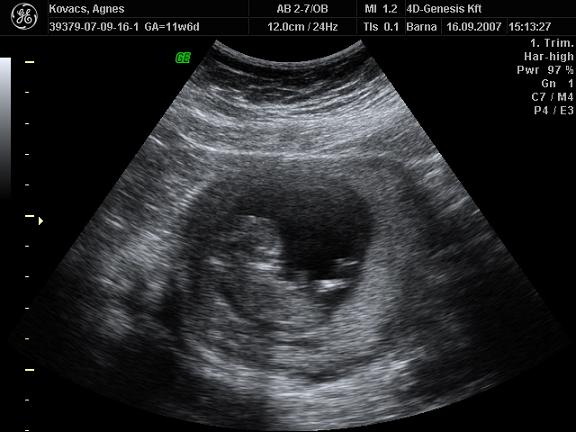

Nos nem tudom, hogy ti mennyire latjatok:

Eleg rosszul latszik, de itt ket vonal van:

Itt meg egy kiallo valami:

Amit lattam az szerintem fiu lesz, hiaba erzem, hogy lany.

A masodik kepen itt nem latszik jol csak a rendes tv-n egyertelmuen olyan mint Zolie volt.

Hiaba van sok helyen ket csikocska.

Nem volt 4D sem es 3D sem, mert meg pici es nagyon eletlen volt.

1 ora volt az UH es vegig mozgott, de beterpeszteni nem akart, ezeket veletlenul csipte el.

magi ehhez hozzátenném, hogy 12 hetes 4D-s uh-on mondta doki hogy ez bizony szép kisfiú,én meg rávágtam az nem lehet, az bizony kislány, mert hogy én azt éreztem. Onnantól kezdve nem mutatta a drágám a 30. hétig, akkor aztán megláttuk, és Réka lett belőle. :):):):):